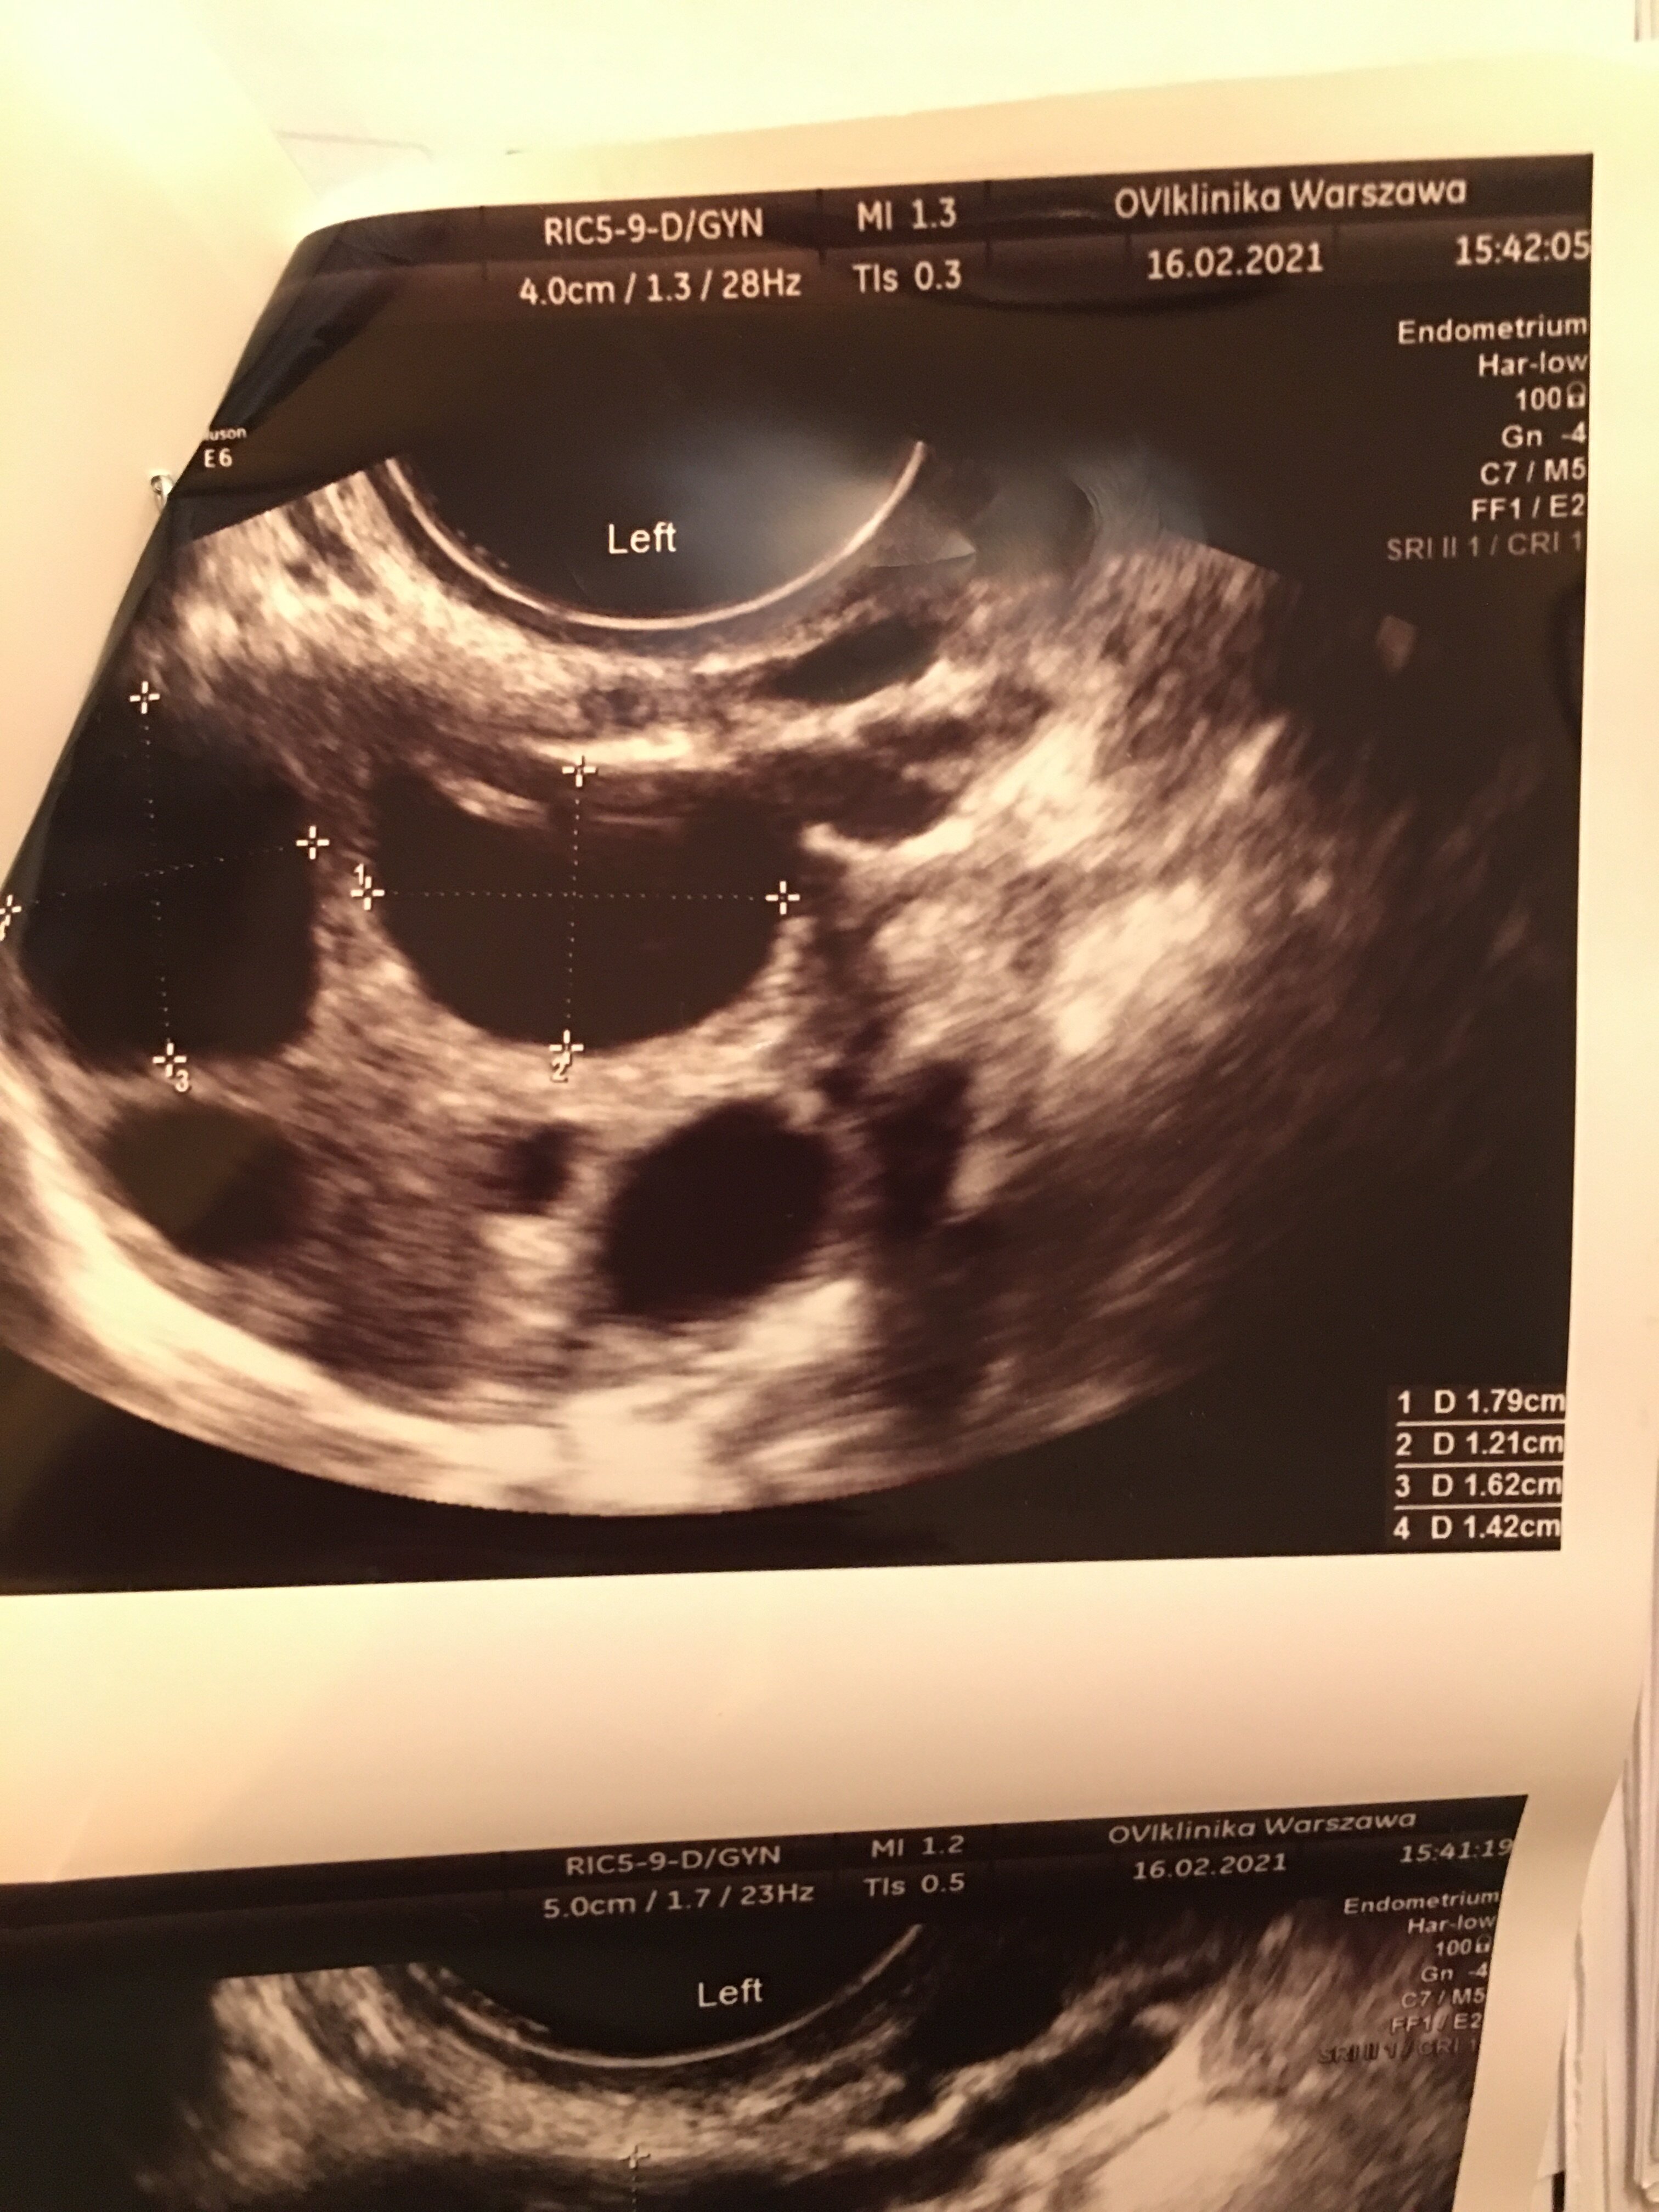

@rossig wlasnie bardzo dużo bo aż 61,90 😨 były dwa pecherzyki

Załączniki

• 2A2DB510-BD31-44CE-B967-B91ACD63C575.jpeg

2A2DB510-BD31-44CE-B967-B91ACD63C575.jpeg

1,2 MB · Wyświetleń: 150